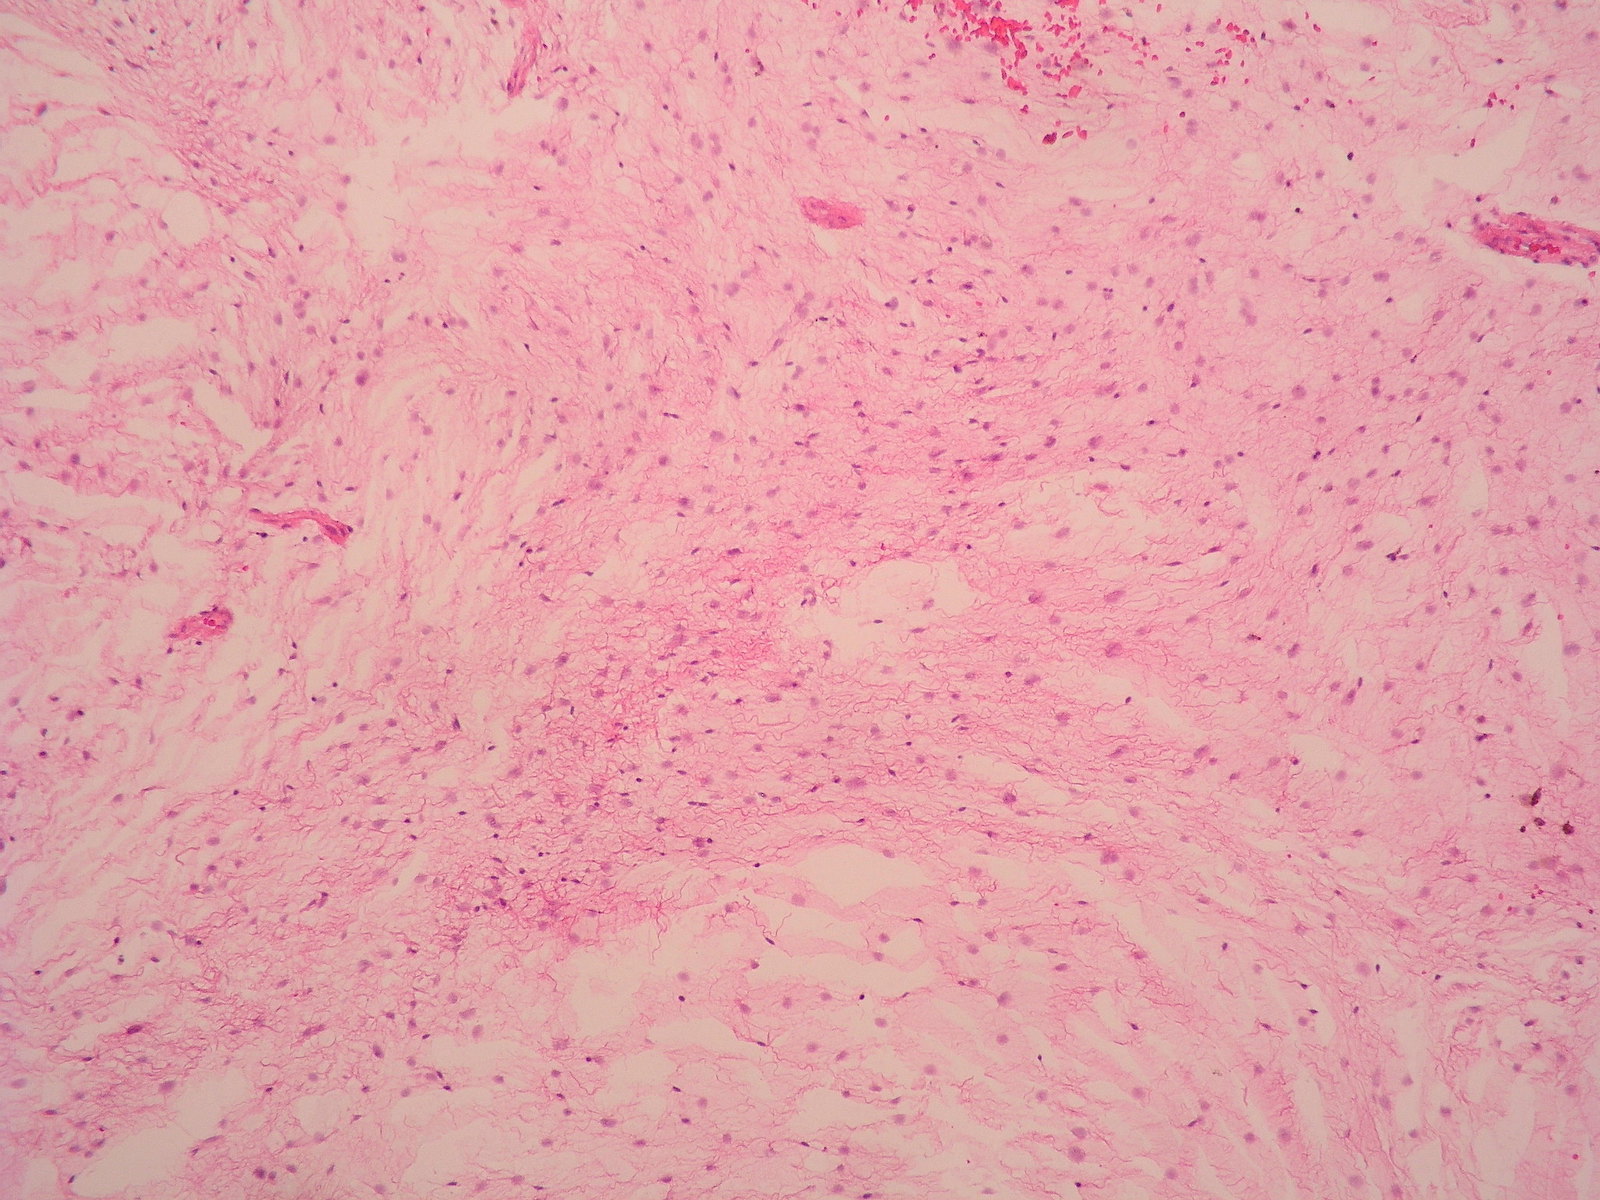

Microscopic (histologic) description

- Low to moderately cellular, bland fusiform or spindled cells with focal to diffuse whirling in heavily collagenized stroma with abrupt transition to myxoid areas

- 45% have epithelioid areas

- 40% contain poorly formed but large collagen rosettes

- Often infiltrates adjacent skeletal muscle

- Occasionally has areas of increased cellularity, atypia, necrosis or mitotic activity characteristic of intermediate to high grade sarcoma

- Recurrences may show increased cellularity and mitotic activity

Microscopic (histologic) images